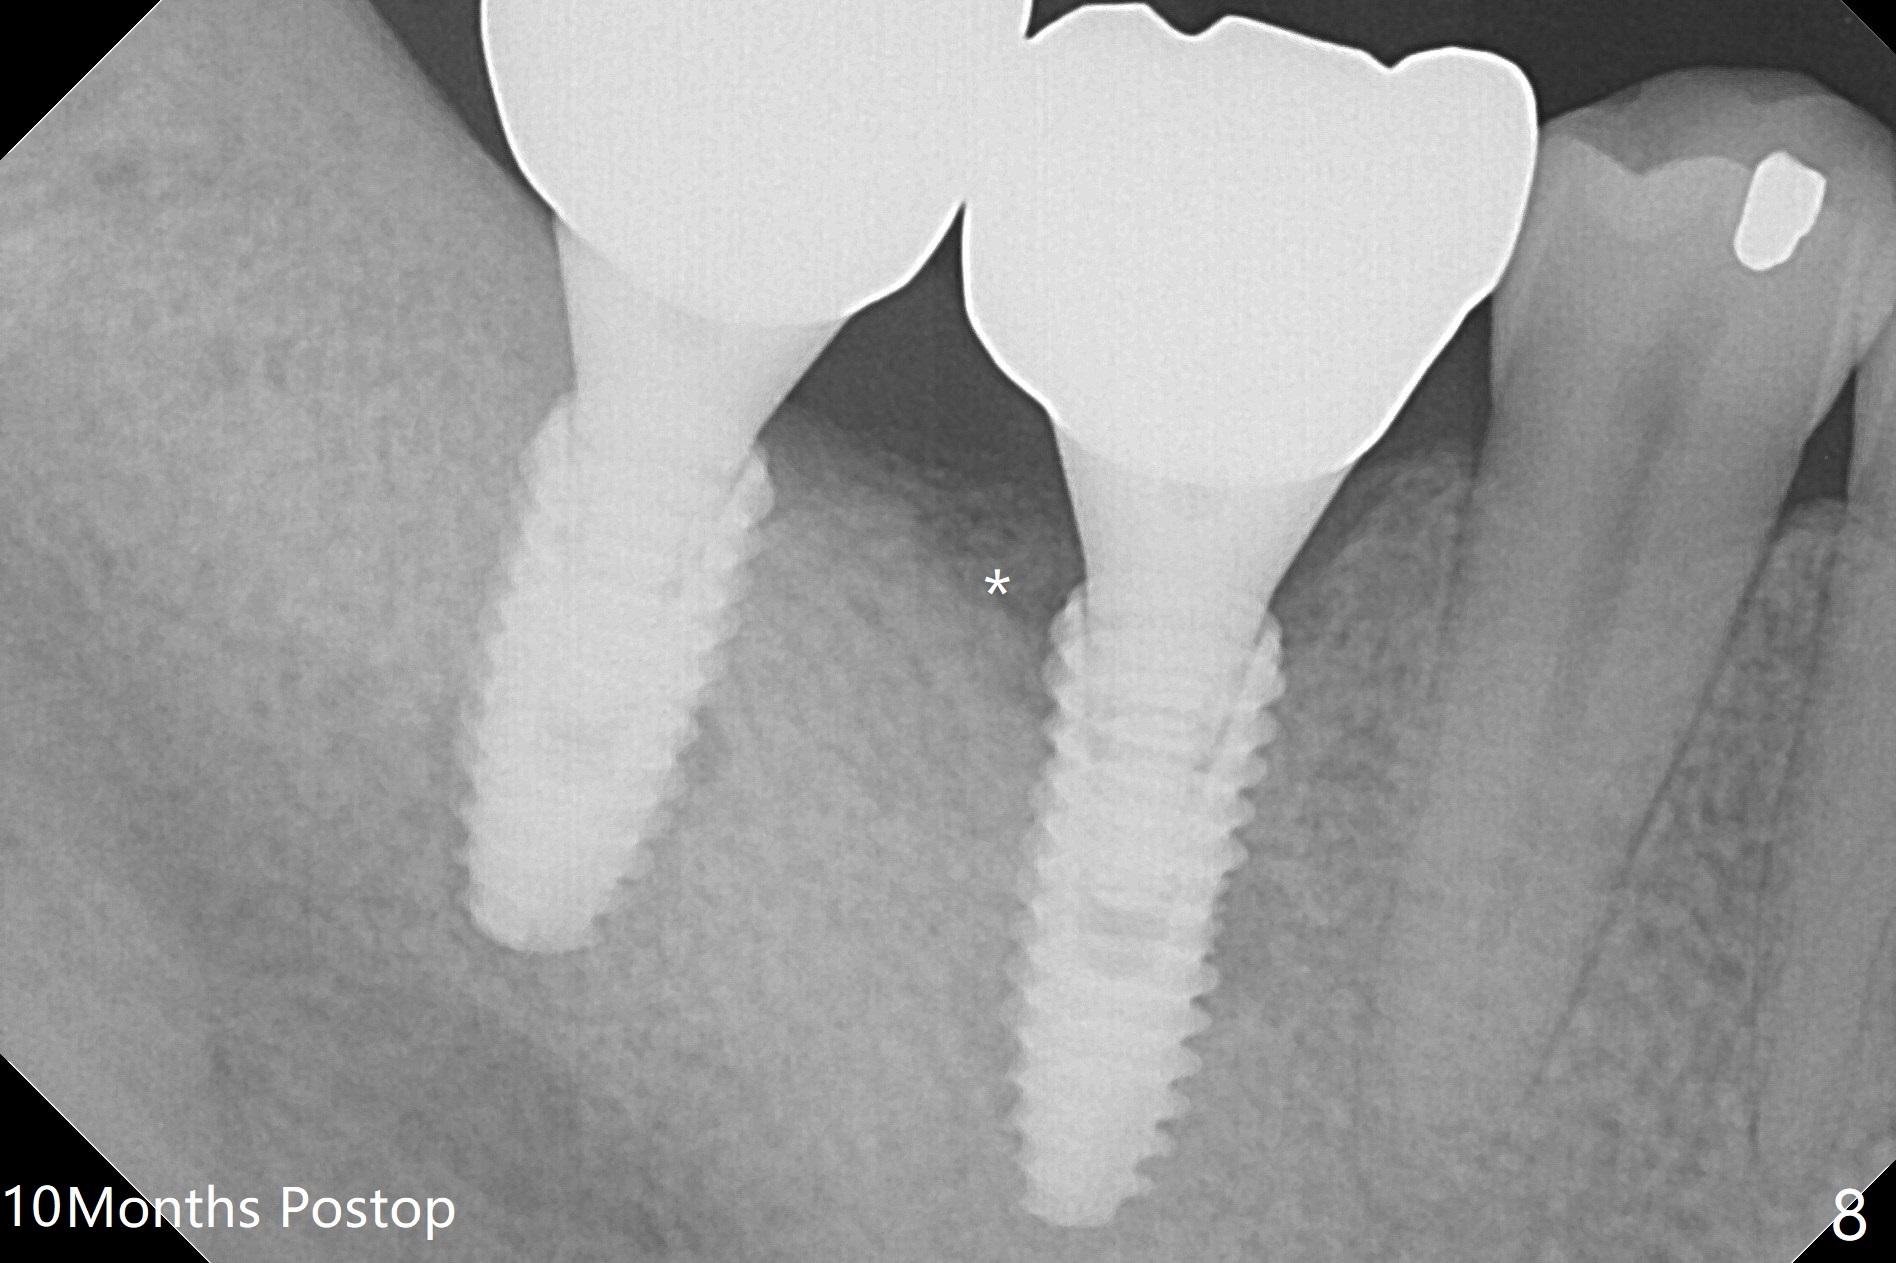

Infection is not so typical.  There is no recent postop X-ray, just 18-19 days postop.   Thanks for the reply.  We will keep watching.  The healing abutments, loose and associated with gingival inflammation, are removed 2.5 months postop (Fig.4).  There is crestal bone resorption, although the implants are stable.  The crestal bone resorption persists especially #30 distal 4 months postop (Fig.5 *).  When the implants are uncovered, there is mild bone loss distobuccal to #30 implant, consistent with early periimplantitis.  Bone graft is placed after debridement and healing abutment placement.  There appears no bone loss nearly 9 months postop (Fig.6).  The soft tissue looks healthy.  Cementation abutments (5.7x4(3) and 5.7x4.5(3) mm at #30,31, respectively) are placed for impression.  The distobuccal gingiva at #30 is hyerplastic 10 months postop (Fig.7 *, immediately before cementation), which is consistent with bone loss (Fig.8,9 * (periimplantitis)).  It is hoped that the infection will dissolve with improved oral hygiene (water pik) over the smooth final restoration.  In fact it is, i.e., the implants at #30 and 31 remain asymptomatic with the healthy gingiva 6 months post cementation (Fig.10,11).  There is mild crestal bone loss at #30 and 31 ten months post cementation (Fig.12).  Crown/implant ratio is the basis for screw loosening.  In fact the crown/abutment at #30 is loose 4 months later.  Incomplete seating of the abutment may be a culprit (Fig.12).  The gingival cuff is not healthy; a 6.8x7 mm healing abutment is placed with gingival blanching with Cetacaine and antibiotic ointment.  Next visit place a new smaller diameter abutment (4.5 or 5.2) with probably longer cuff (4 mm) or the existing abutment with no proximal contact crown, torque 25-30 Ncm and take BW with sensor 2 or PA with sensor 1.  In fact there is resistance to hand tighten a 4.5x4(4) mm healing abutment, which is due to contact with the mesial crest (Fig.13 *).  After use of 5.5 and 6.0 mm profile drills, the 6.8x7 mm healing abutment is reseated.  The latter appears to contact the mesial crest (Fig.14).  Later a 6x5 mm healing abutment is placed.  New crowns with new abutments are delivered 2 years 3 months postop (post Coronavirus lockdown).